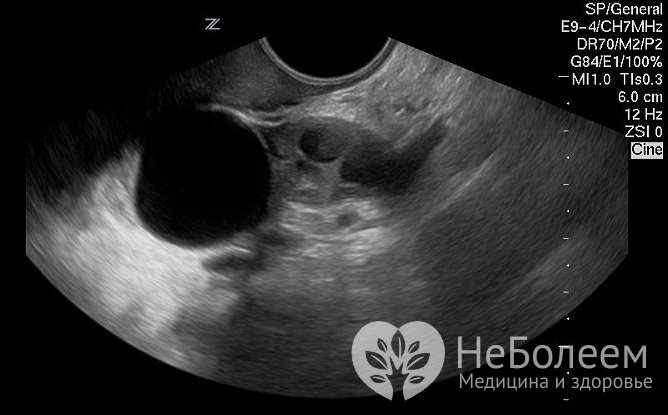

Фолликулярная киста яичника хорошо просматривается на УЗИНеобходима дифференциальная диагностика с кистомой яичника, внематочной беременностью, злокачественным новообразованием яичника, воспалительными заболеваниями мочеполовой системы, острым аппендицитом.